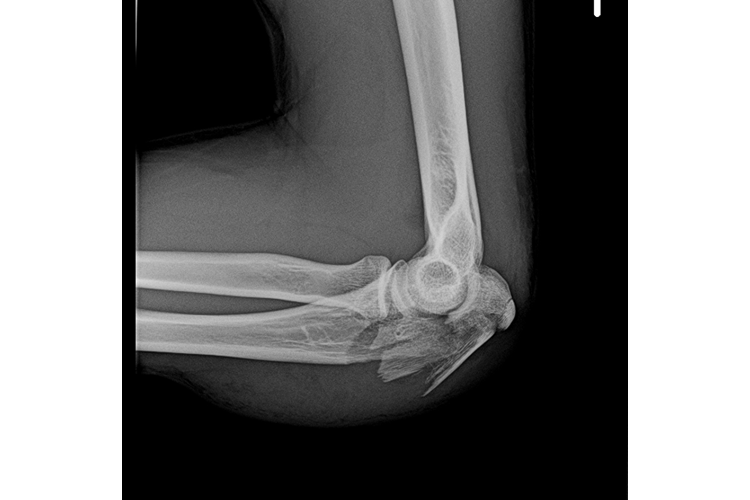

Našim aktivnostima se kao partner pridružio Klinički bolnički centar Osijek, koji objašnjenjem ozljeda i prikazom RTG snimaka ukazuje na česte situacije nastanka teških tjelesnih ozljeda nakon pada s e-romobila

Ovakve preventivne aktivnosti dio su šireg plana podizanja prometne kulture, smanjena broja prometnih nesreća s ozlijeđenim vozačima bicikala i osobnih prijevoznih sredstava, kao i padova prilikom gubitka ravnoteže, najčešće zbog neprilagođene brzine kretanja djece i mladih, kojom prilikom dolazi do težih tjelesnih ozljeda poput frakture lubanje, kostiju ruku, nogu i drugih dijelova tijela, a što se edukacijom i informiranjem želi u budućnosti spriječiti kako bi takvih ozljeda bilo sve manje. Našim aktivnostima se kao partner pridružio Klinički bolnički centar Osijek, koji objašnjenjem ozljeda i prikazom RTG snimaka ukazuje na česte situacije nastanka teških tjelesnih ozljeda nakon pada s e-romobila.